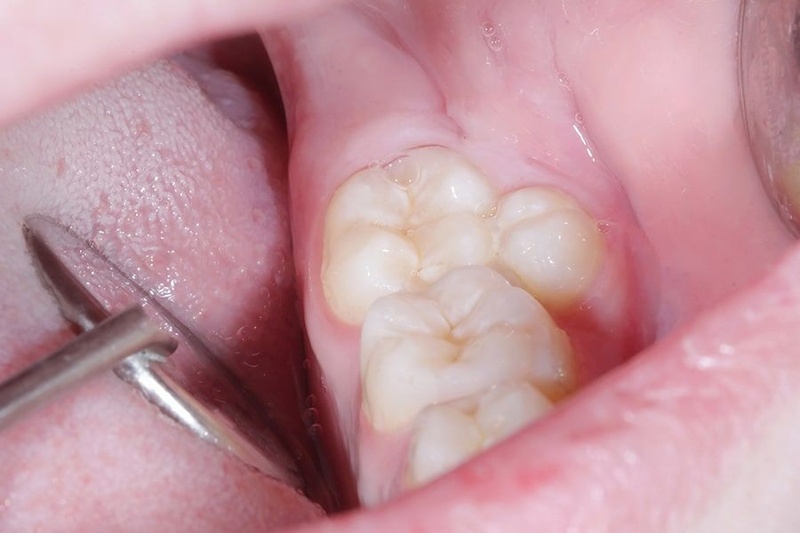

- Các dạng mọc thừa phổ biến khác: Răng khôn, răng khểnh, răng mọc lẫy, răng mọc thừa ở vùng răng hàm.

- Răng mọc không đúng vị trí: Đây là dấu hiệu dễ thấy nhất. Bạn có thể thấy một chiếc răng mọc chen vào giữa hai răng cửa (gọi là Mesiodens), mọc lệch hẳn ra ngoài hoặc vào trong cung hàm (răng khểnh, răng mọc lẫy).

- Hình dạng răng bất thường: Răng thừa thường có kích thước nhỏ hơn, dị dạng, có hình nón hoặc hình củ, không giống hình dạng của răng bình thường.